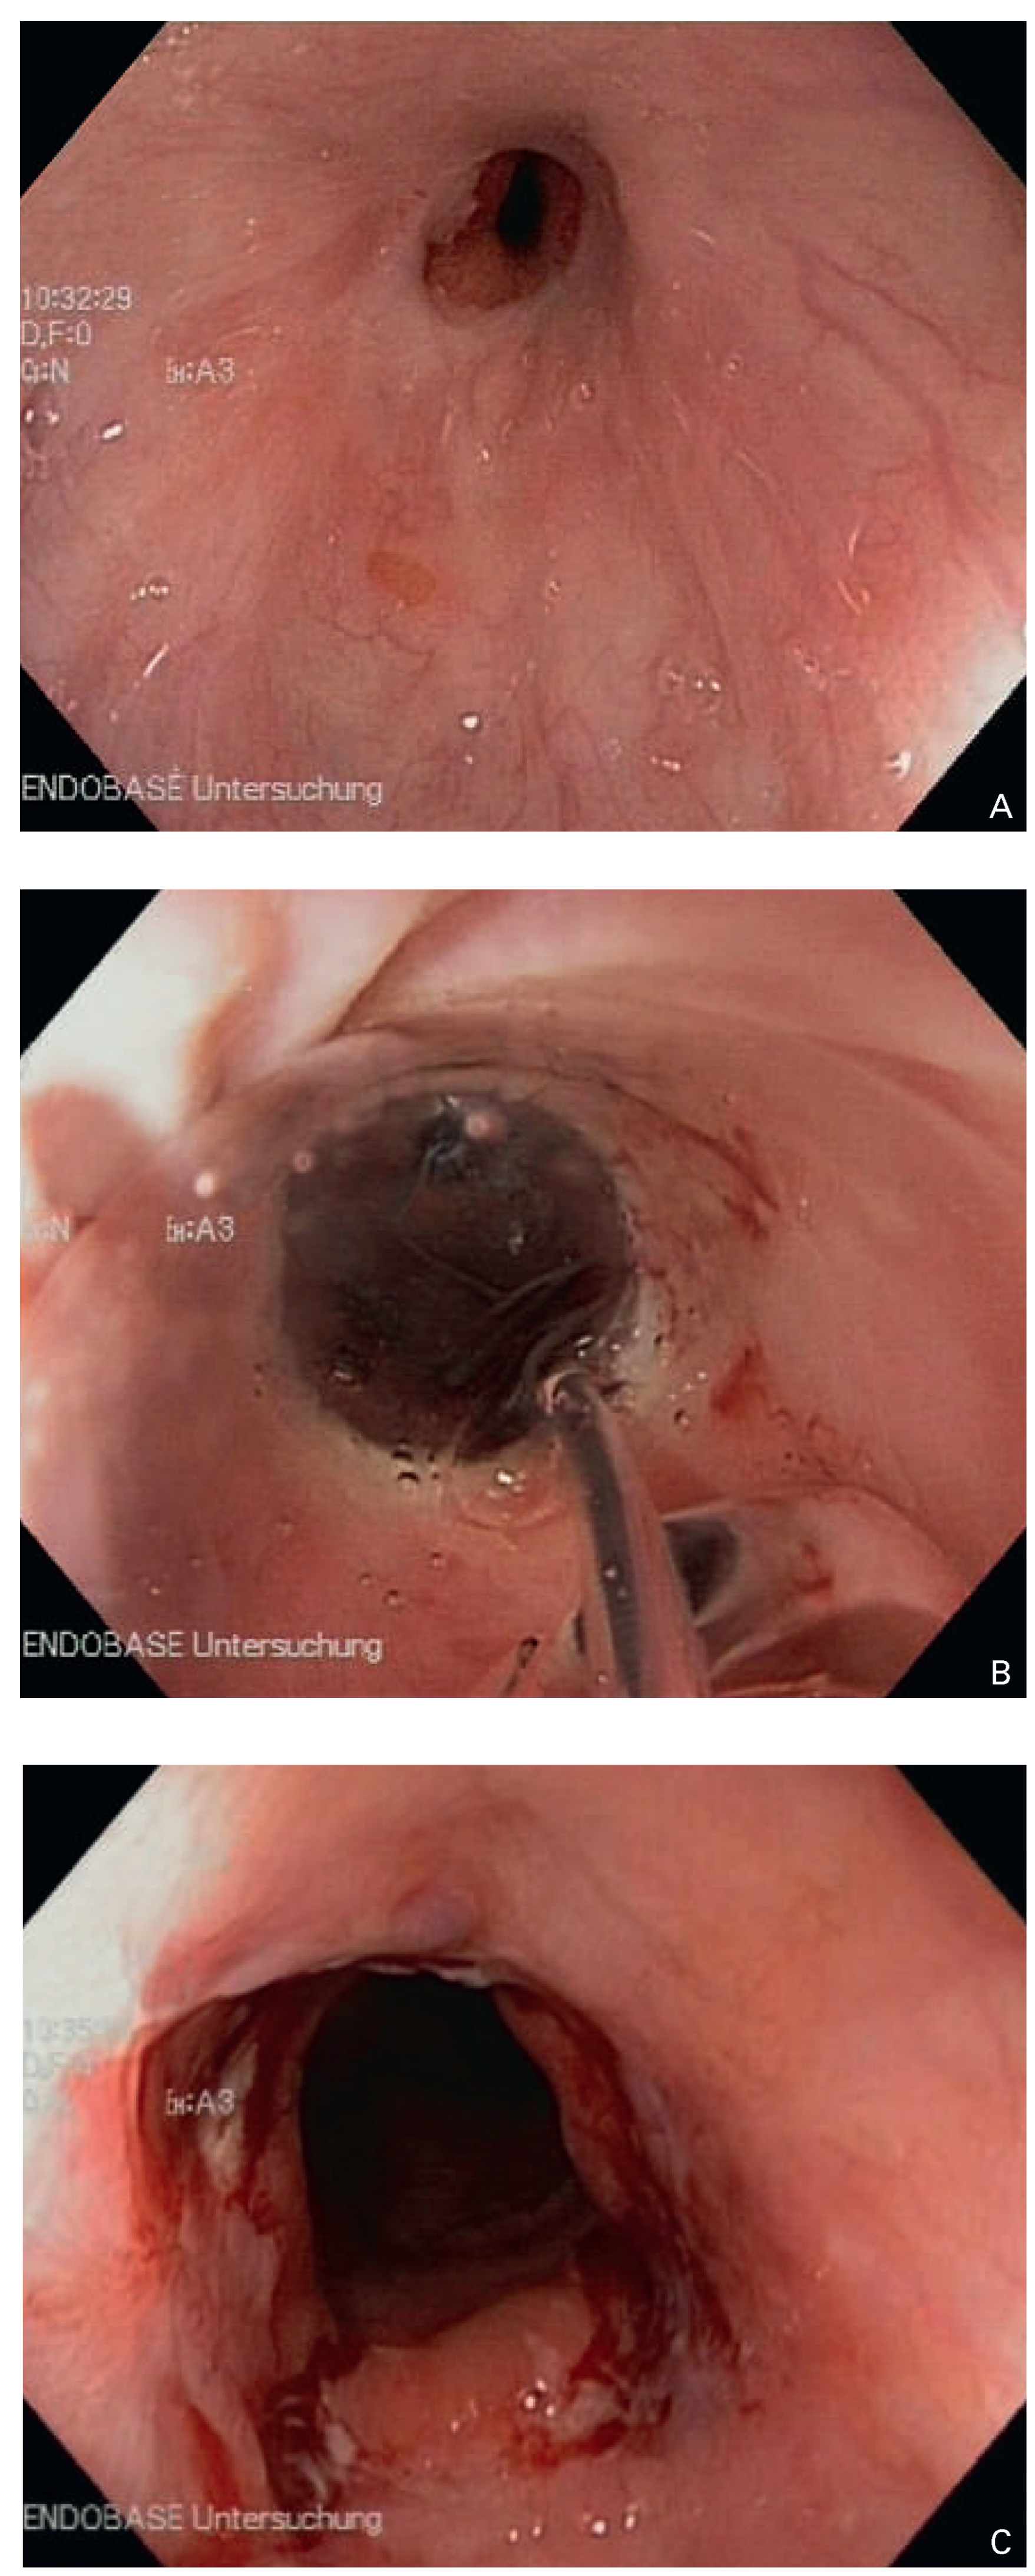

Die häufigste strikturierende Pathologie ist die peptische Stenose als Folge einer gastroösophagealen Refluxkrankheit [6]. Saurer Reflux in hochgradig pathologischem Ausmass führt zu Ulzerationen am gastroösophagealen Übergang. Die chronische, bisweilen zirkulär ulzerierende Refluxösophagitis, aber auch der Abheilungsprozess derselben unter säuresekretionshemmender medikamentöser Therapie, kann zu sanduhrförmigen Lumeneinengungen führen (Abb. 1A–C). Nicht selten resultiert eine höhergradige narbige Stenose, die mit dem TEE-Instrument – und desgleichen mit dem Gastroskop – nicht mehr passierbar ist. Klassischerweise deutet ein charakteristischer Symptomwandel auf eine solche Krankheitsprogression hin, was dem aufmerksamen Arzt nicht entgehen sollte. Die vormals quälenden, meist langjährigen Refluxsymptome (saures Aufstossen, Magen-/Sodbrennen) verschwinden und gehen über in eine Dysphagie (Schwierigkeiten beim Schlucken, Steckenbleiben und Hochwürgen von Nahrung). Als effiziente Behandlungsmethode steht die endoskopischen Bougierung zur Verfügung, parallel zur medikamentösen säurehemmenden Therapie (gefolgt von einer Dauerrezidivprophylaxe) mit einem Protonenpumpeninhibitor.

Abbildung 1. Ösophagoskopische Befunde bei gastroösophagealer Refluxkrankheit. (A) Ulzerierende Re-fluxösophagitis, (B) mässiggradige peptische Stenose, (C) zirkulär ulzerierende Refluxösophagitis mit höhergradiger Stenose.